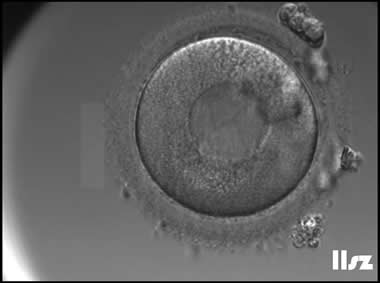

3. 成熟卵母细胞(MII)及其COCs(正常COCs)

卵细胞呈现规则的圆形且颜色较浅,放射冠完全分散,颗粒细胞团较大,排列稀疏。成熟卵母细胞一般在取卵后体外培养2-6小时再行授精。

|  |

| 0小时COCs的MII卵(4x) | 0小时COCs的MII卵(10x) |

|  |

| 2小时COCs的MII卵(10x) | 4小时去颗粒细胞后的MII卵(10x) |